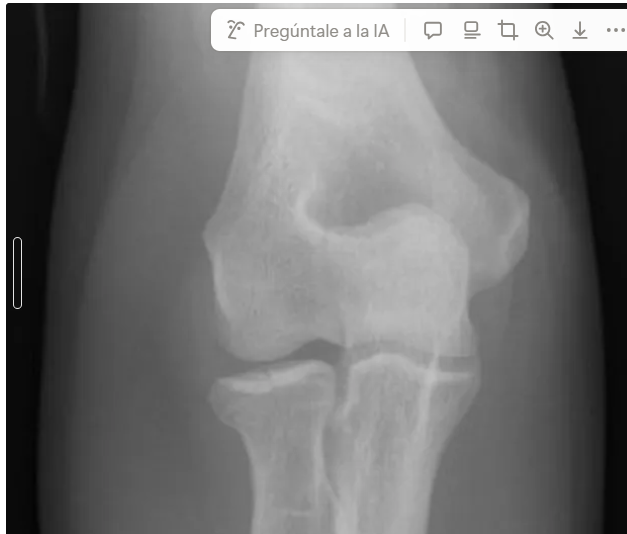

segun clasificacion de Masson que tipo es

tipo 2